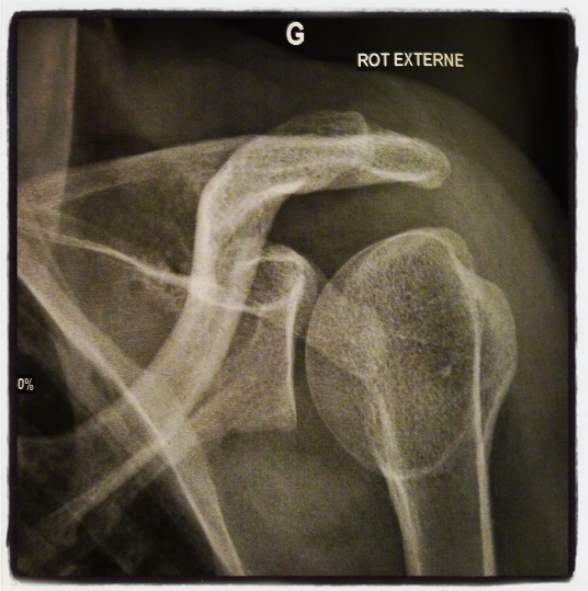

Admirez ce splendide humérus

Mon généraliste m’a fait ce qu’on appelle un palm test et prescrit une radiographie assortie d’une échographie de l’épaule gauche, pour voir de quoi il retournait réellement. Le seul double rendez-vous disponible avant qu’il ne parte en congés plusieurs semaines tombait à deux jours de la date de remise de mon énorme trad (terminée, elle devrait faire dans les 1140 pages) et m’obligeait à me rendre dans une clinique de l’autre côté de la ville. Investissement: au moins trois heures du précieux temps qui me restait. Tant pis, je voulais en finir, recommencer à bouger normalement et à aller à l’aerial yoga – fût-ce sans retenter les planches latérales à l’avenir.

Hier en fin d’après-midi, donc, j’ai vu un charmant radiologue qui m’a demandé de lui montrer dans quelles positions j’avais mal. Et là, grand moment de solitude. J’ai eu beau faire rouler mon épaule, tourner et plier mon bras dans tous les sens: rien. Nada. Nichts. Des nèfles. Même pas une petite gêne symbolique. Le gars a dû me prendre pour une illuminée qui aimait gaspiller son temps et l’argent de la sécurité sociale. Je me suis rhabillée en bredouillant des excuses incohérentes et j’ai filé avec mes radios où toute lésion brillait par son absence. Je me suis dit que bon, au moins, ce n’était pas une capsulite comme ma mère en a eu une, que j’échappais au combo intervention chirurgicale et immobilisation subséquente pendant un mois et demi, et que de toute façon, si le ridicule tuait, je serais déjà morte plus de fois que Kenny dans South Park.